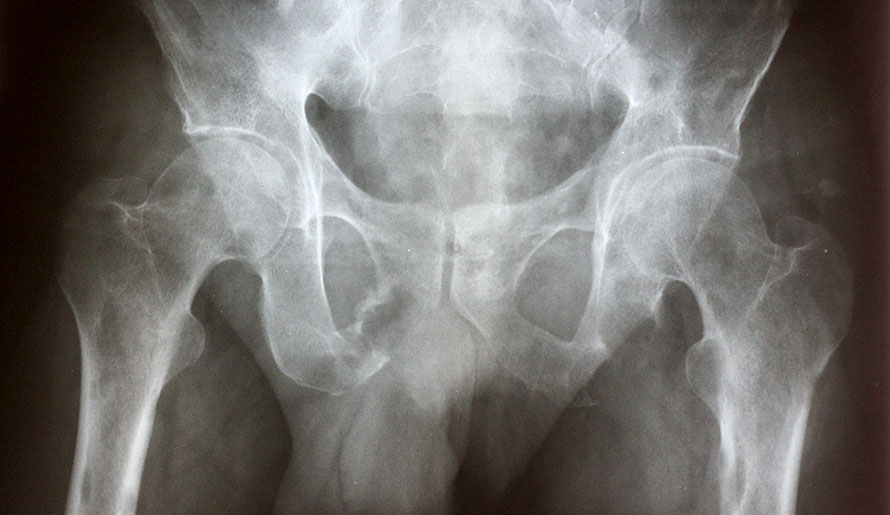

x-ray of pelvis bone

Leaders in the Use of Navigated Bone Tumor Resections and Custom Implant Reconstruction

Increasing research demonstrates that navigated resections, especially in complicated locations like the pelvis, can improve cancer-specific...